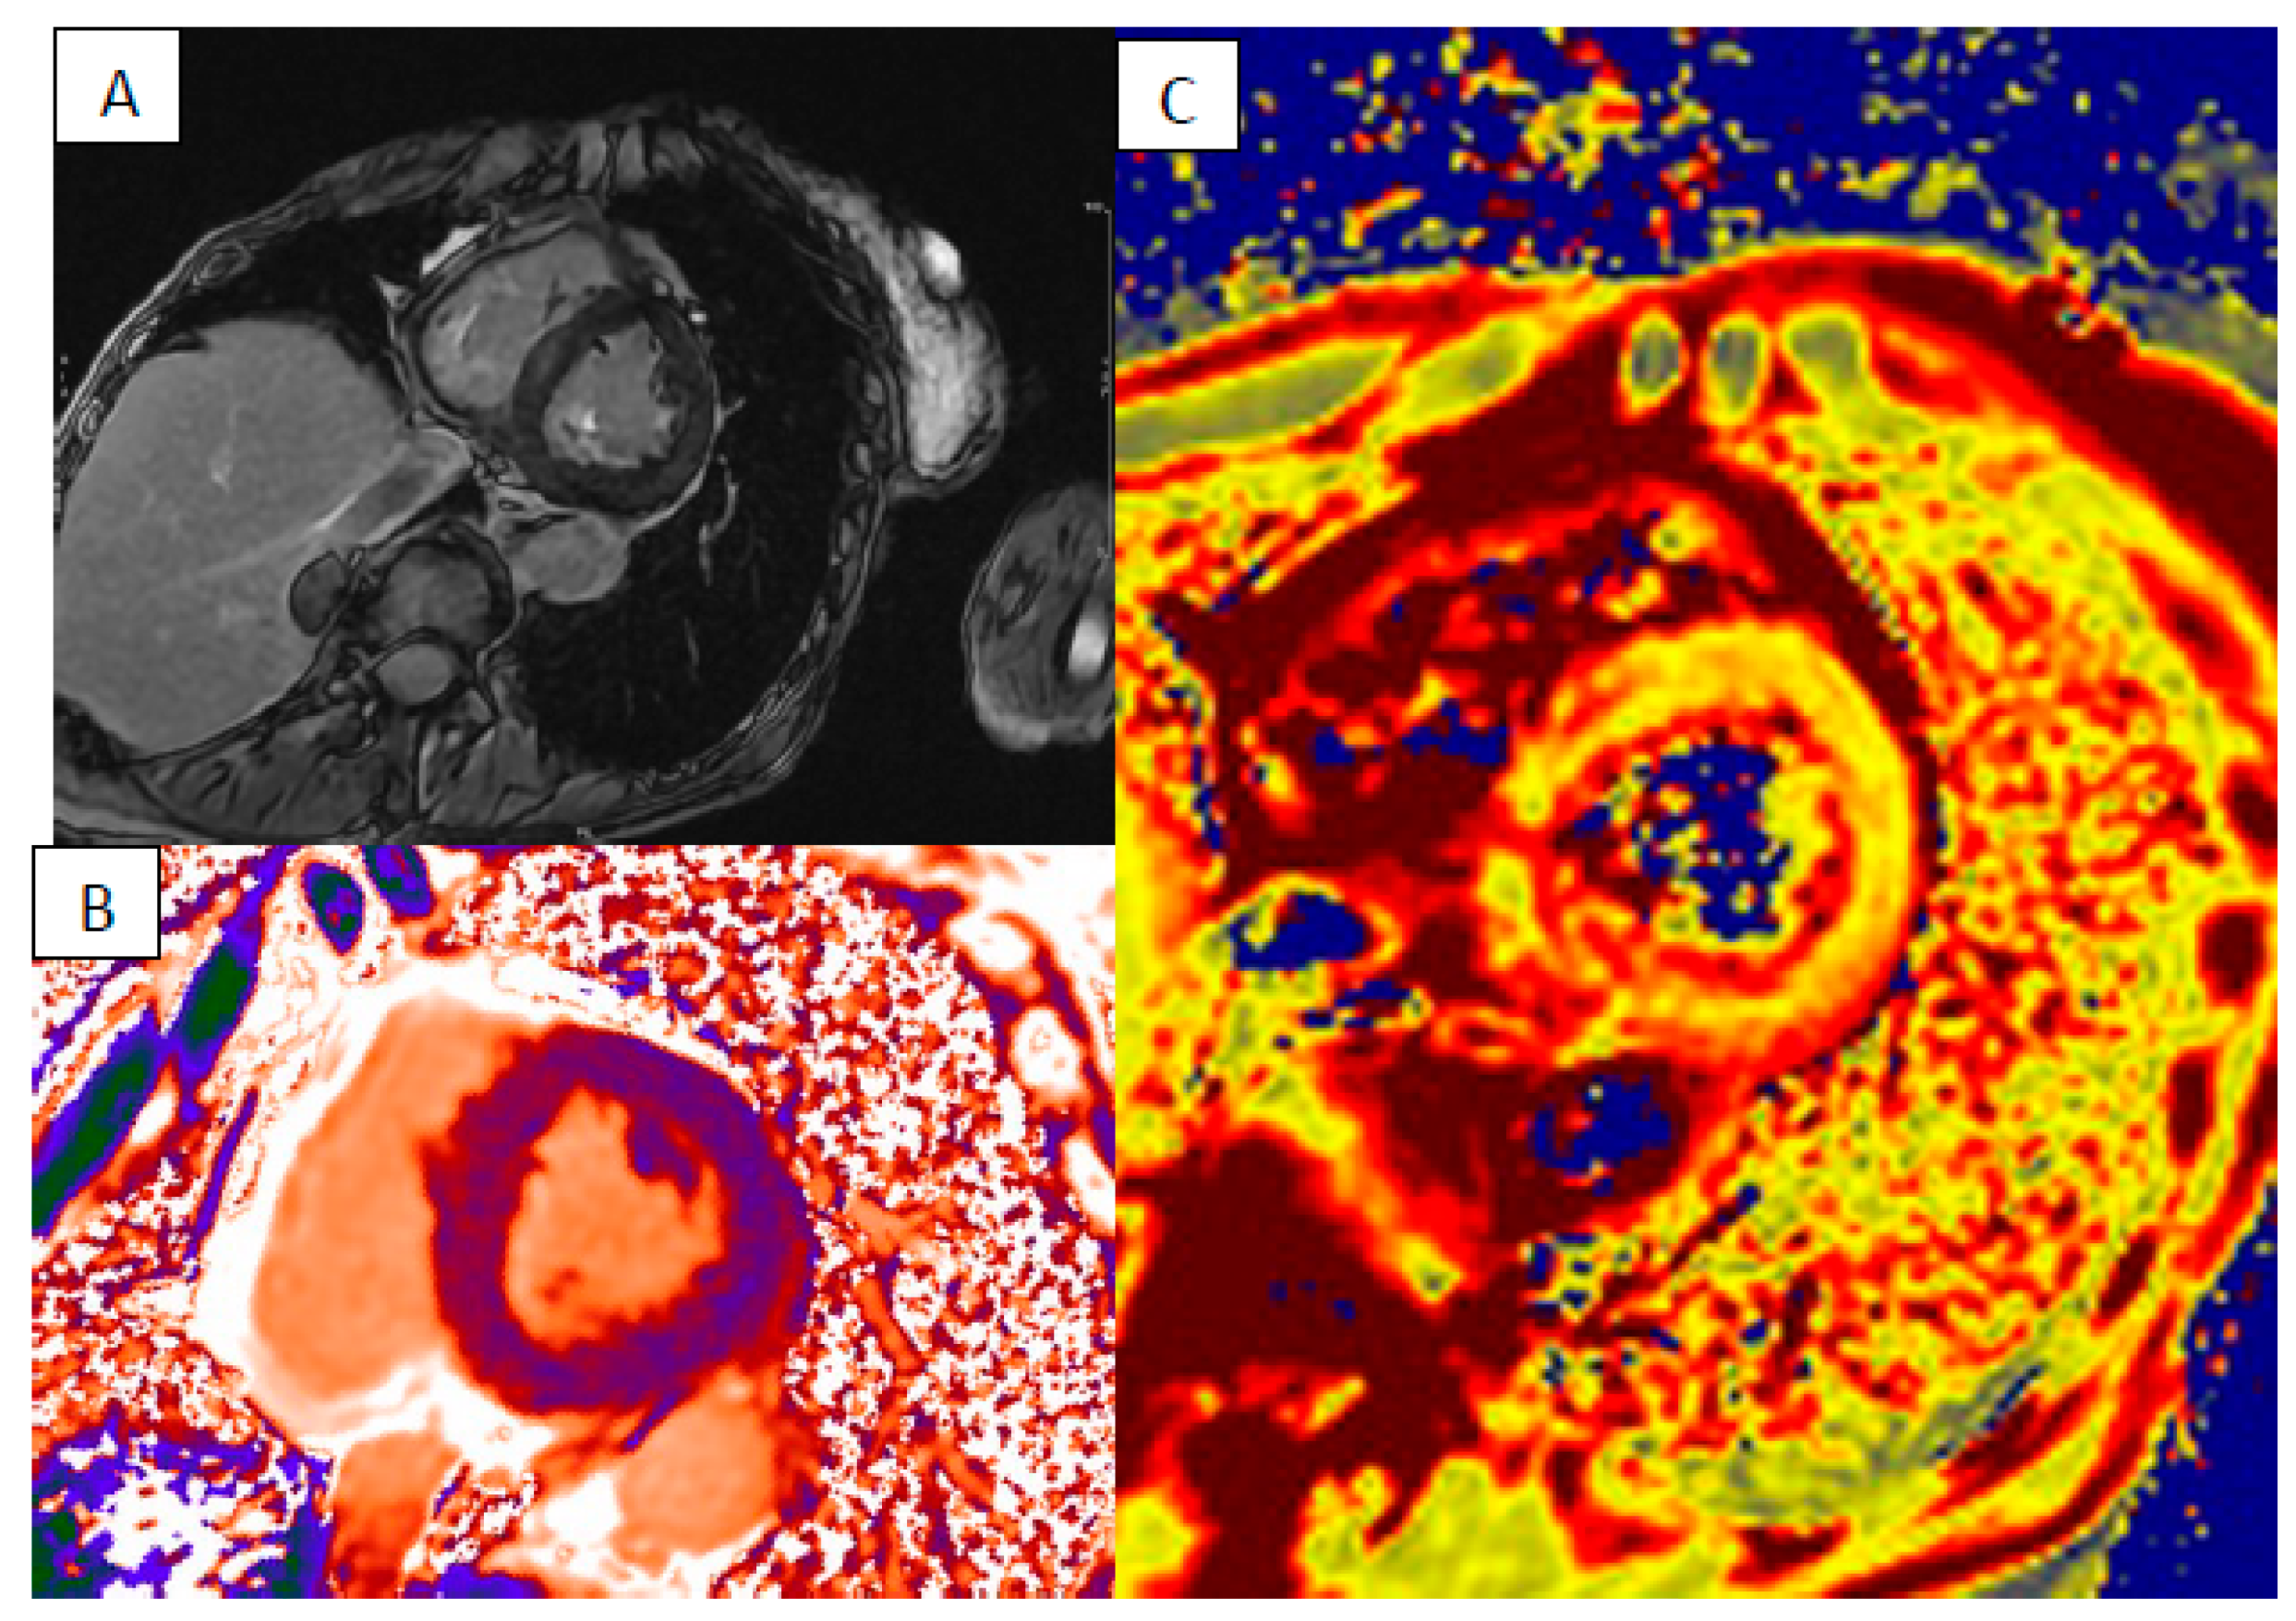

4. Cardiac Amyloidosis